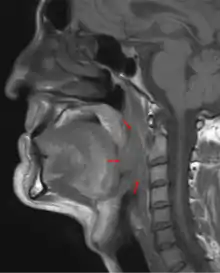

Oropharyngeal cancer (from right tonsil, HPV-negative), T4a N2c, 48-year-old man.